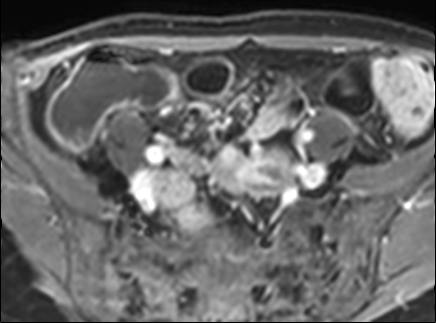

Bệnh nhân nữ 48 tuổi, đang điều trị bằng thuốc kháng TNF, được chỉ định nội soi đại tràng.

Phát hiện hẹp lòng ruột ở đại tràng sigma, không thể vượt qua được khi nội soi.

MR-enterography được thực hiện để đánh giá mức độ lan rộng của chỗ hẹp.

Ruột non bình thường, nhưng ghi nhận các đoạn hẹp ở đại tràng xuống và đại tràng ngang.

Cả hai đoạn hẹp đều có thành ruột dày đến 8 mm và ngấm thuốc rõ rệt theo kiểu niêm mạc ở đại tràng xuống và kiểu phân lớp ở đại tràng ngang.

Giãn ruột trước chỗ hẹp được ghi nhận ở cả hai đoạn.

Do các chỗ hẹp này không hiện diện khi nội soi đại tràng trước khi điều trị kháng TNF, nhiều khả năng chúng đã hình thành trong quá trình điều trị.

Do đó, quyết định phẫu thuật cắt đại tràng gần toàn bộ với miệng nối hồi-sigma đã được đưa ra.